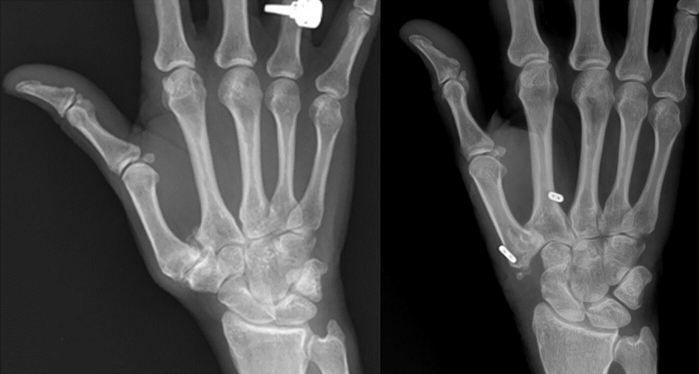

手術治療方式會根據病患的年齡及嚴重度而調整,包括微創關節鏡手術、關節融合、大多角骨切除合併韌帶重建或人工韌帶懸吊,人工關節置換等等。

2010年美國史丹佛大學Jeffrey Yao教授發表了縫線鈕扣懸吊(suture button suspensionplasty)的手術方式治療基底關節炎,利用懸吊固定掌骨進一步增加關節穩定度,配合關節鏡微創手術進行。研究發現懸吊手術術後的復原較快,大拇指活動度及病人滿意度都相當高。